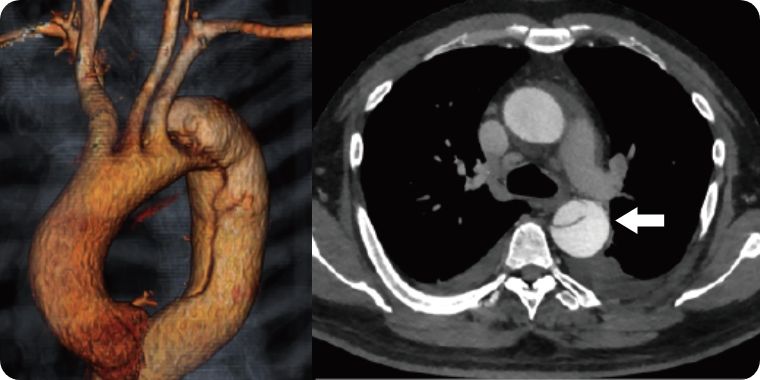

大動脈解離は、突然発症する疾患で、大動脈に亀裂が入り、血管が裂ける病気です。急性期には解離した血管壁が薄くなり、破裂を起こす可能性や主要臓器への血流が遮断されることで臓器障害を引き起こす可能性があります。治療法は、動脈瘤と同様に人工血管置換術とステントグラフト内挿術があり、病態に合わせて適切な治療を行います。

解離した場合によっては、ステントグラフト治療が適応になることがあります。大動脈解離に対するステントグラフト治療は専門性が高く、心臓血管に特化した当院の大動脈専門スタッフが慎重に判断して施行しています。

白矢印が大動脈の亀裂、赤矢印はステントグラフトで亀裂を閉鎖していることを示す。